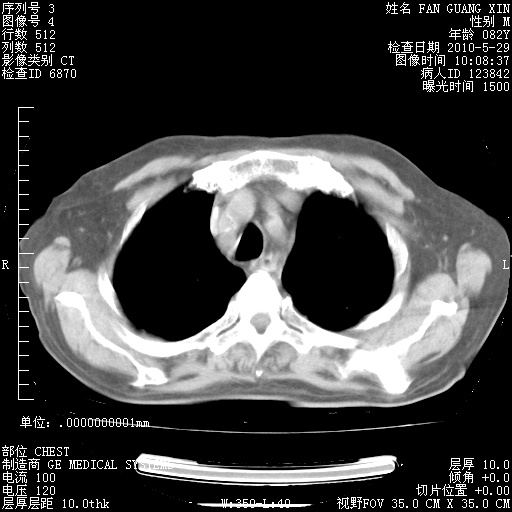

再治疗10天后的肺部CT 纵膈窗

阅读此次胸部CT,肺间质渗出性改变较入院时有吸收。目前从体温、白细胞、中性分叶明显增高,肯定存在细菌感染(发生医院感染哦,若无消化道及泌尿系统等感染的依据,肺部感染可能大)。若你院头孢哌酮舒巴坦钠耐药率较高,同意你的方案,若48小时体温仍高,可考虑使用碳青霉稀类抗菌药物,同时可予超声雾化、注意滴数时加大液体量。白蛋白33.30g/L较低哦,需加强营养等支持治疗。